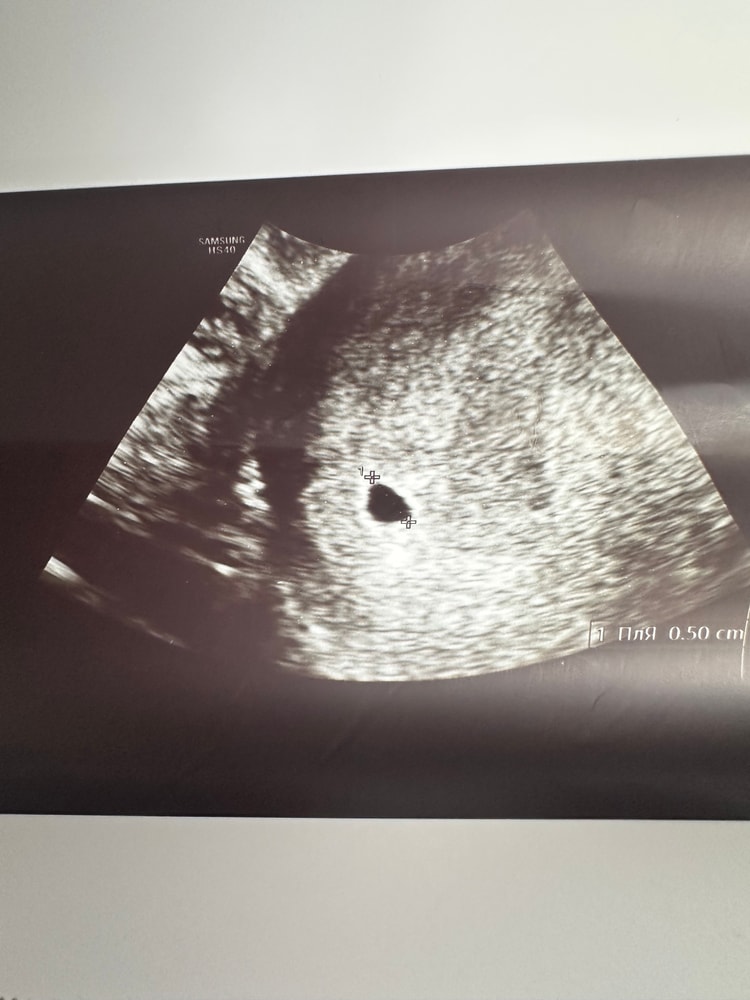

УЗИ 4+6

Поэтому побежала на УЗИ,чтоб увидеть что-нибудь🙈

Увидела:

ПЯ 5мм

ЖТ 22*16

Прикрепление по передней стенке

Соответствует сроку 4-5 недель)

Наше первое фото😀♥️: